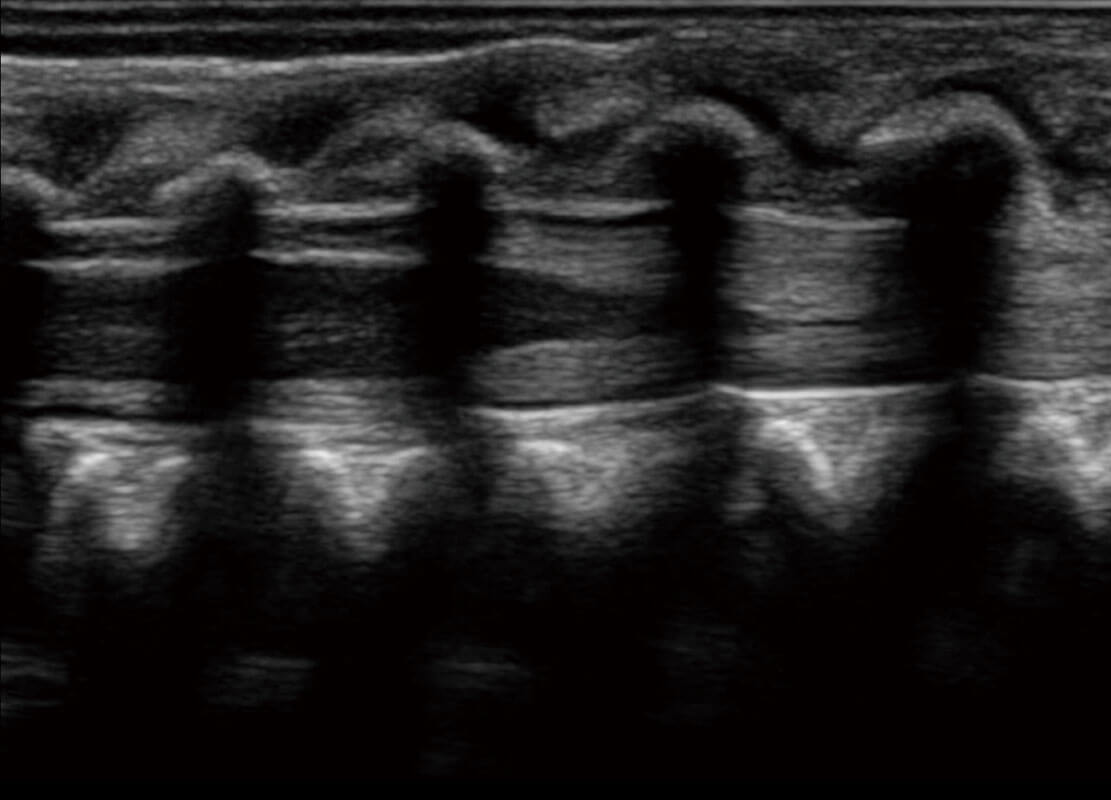

四腔切面

四腔心血流